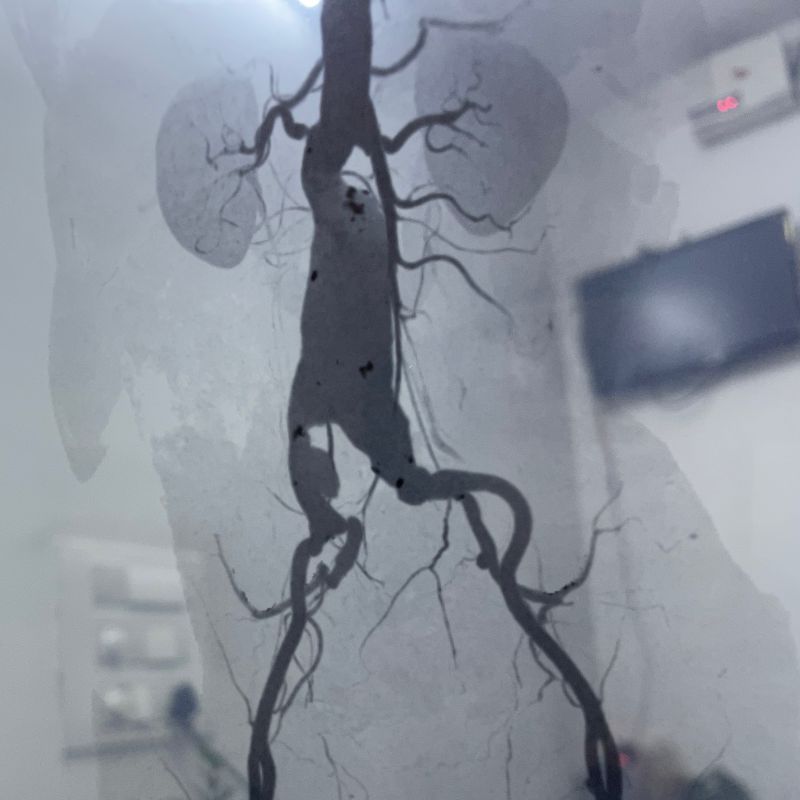

Abdominal Aaortic Aneurysm

Abdominal aortic aneurysm:

This can occur in the part of your aorta that passes through your abdomen. There are usually no telling signs to warn you that something is wrong.